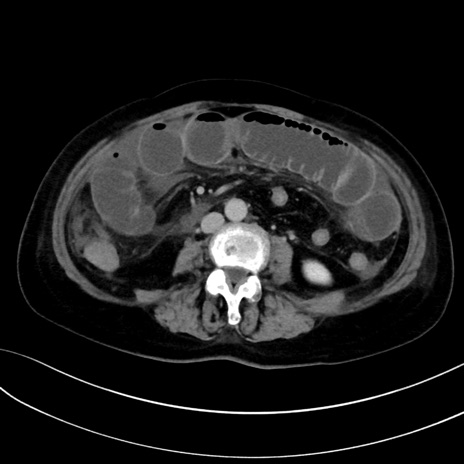

症例13 CT(横断像)1日半後